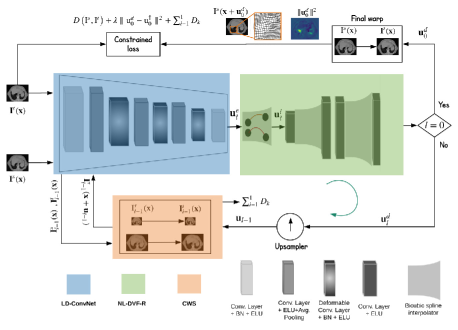

As motivated, we now introduce the key elements to our Conv2Warp model (each highlighted in Fig. 1), and describe our constrained loss function.

Linear and Deformable Convolutional Network (LD-ConvNet)

LD-ConvNet (blue block in Fig. 1) consists of 5 linear convolutions and 3 deformable convolution layers. Each convolution layer is combined with a batch normalization and ELU activation function. After the second convolution layer an average pooling layer with downsampling factor of 0.5 is applied. Throughout we use a sequential ConvNet of (input, output) channels as follows: , , , , , , , with kernel size and stride 1. Two images (source) and (target) are concatenated first and set as an input to the first layer of the Conv2Warp model.

Non-linear DVF Resampler (NL-DVF-R)

NL-DVF-R (green block in Fig. 1) consists of a sequential bicubic Catmull-Rom spline resampler and convolutional filter for resampling the obtained DVF from the LD-ConvNet. Since, this is integrated in our learning model, complex non-linear deformations learnt by the LD-ConvNet are guaranteed to have smooth deformation fields and the interpolation error is minimal.

Continuous Warping Stage (CWS)

CWS (orange block in Fig. 1) warps the deformation field obtained at pyramid levels in a continuous fashion. Here for our 2D case with image size and for our 3D case with patch volume size . Note that pyramids are constructed prior to feeding images into the LD-ConvNet.

The CWS employs warping of the next level source image with the computed DVF from previous coarse level LD-ConvNet, i.e., . This process is repeated until the final level, i.e., . At each level the losses between the warped image and the target are summed and transferred to the final constrained loss function detailed in the Section 2.

Loss function

A multi-modal normalized cross-correlation (NCC) metric is used as data term in our loss function. We propose to use a derived sum-of-squared difference (SSD) which guarantees maximization of NCC metric [4] and is written as with mean , standard deviation , the total number of pixels and (used to avoid division by zero). For obtaining a smooth deformation vector field we apply an -norm of the difference between the computed from the NL-DVF-R block and which is the previous upsampled input DVF to CWS block (see Fig. 1). Losses computed during pyramid levels in our CWS block are aggregated to the final loss. The resulting equation for the backward propagation is: where is the trade-off between the regularization and the data-term. In our experiments it is set to 0.001. We restrict the regularization to the interval to prevent over smoothing problem during training. Omitting this constraints results in failures which are documented in Fig. 2 of Suppl. Mat. (see plot for Conv2Warp-FullReg). The loss saturates after 6000 iterations. However, regularised models with the interval continue to minimise the loss function. Our constrained loss is optimized using Adam optimizer with learning rate .